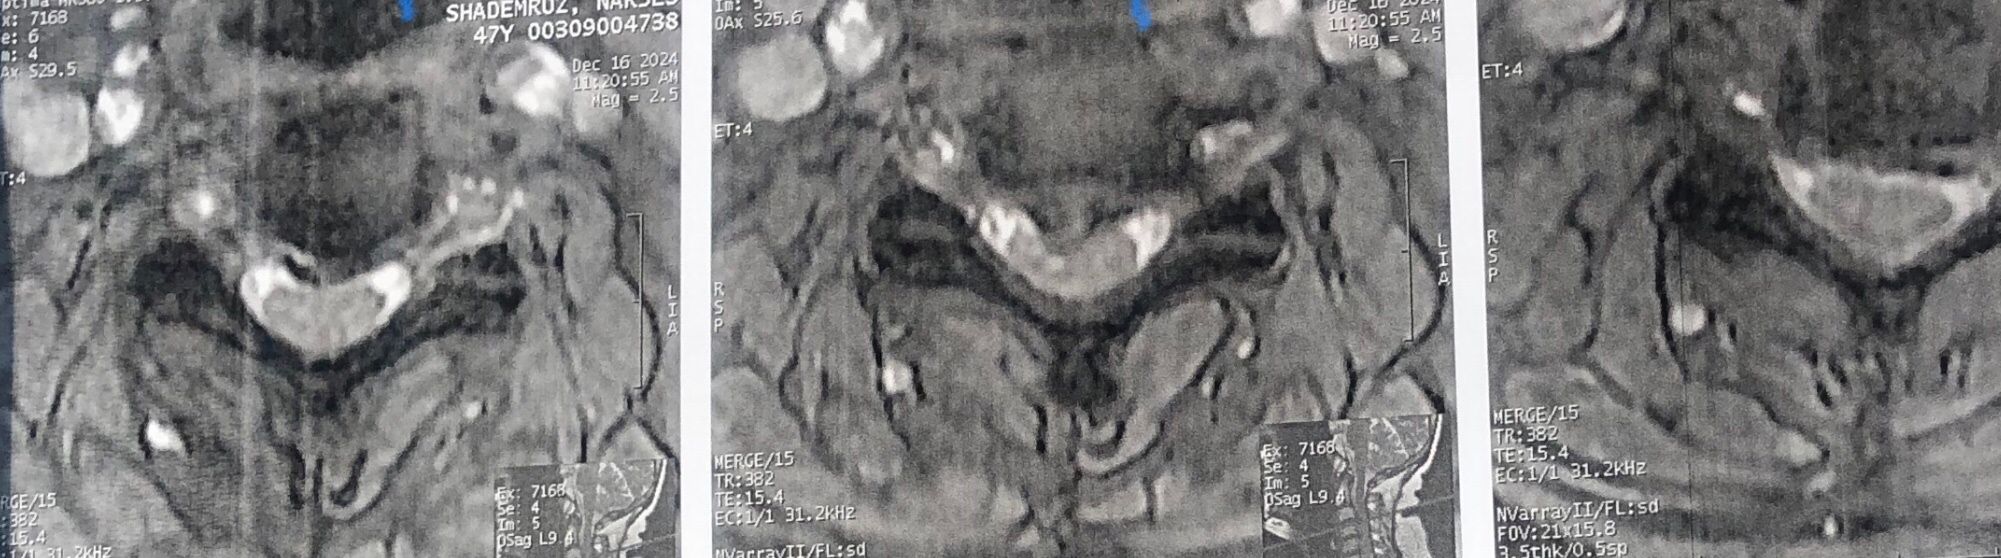

41 years old man presented to my clinic in October 2023 with acute and sever R neck pain with radicular pain to his R upper extremity along C6 dematom since 2 weeks ago. Examination didn’t show any upper motor signs. Was suggested urgent surgery

I ordered EMG/ NCV : showed mild R C6, C7 irritation without any active axonal loss

In his MRI was reported R. para R. IVF Massive extrusion. I decided to control his pain and manage this patient with reevaluation of patient every other session. For 5 sessions i just used acupuncture and laser and IFC and mild adjustments to his R. T3-T7 and mild arthosteem to above and below involved segment. Cervical adjustment considered contraindicated for this patient. From session 6th- 8th i started to use mild/gentle cervical decompression. He used soft cervical collar all the time. His pain decreased by 80 percent

I gave him cervical traction pump to be used 3-5 times per day at home for the next 3 months and i released the patient. He was evaluated every week once for one month and after that every 2 weeks. After 3 month I repeated MRI. Size of the herniated disc was reduced greater than 50 percent. Asked him to do another mri in 6 months

In general: Precise selection of the patients, examination,diagnosis, plan of management, reevaluation and treatment can be done by doctors of chiropractic for the patients with spinal disc herniation and stenosis Moreover giving reasonable time to these kind of patients under direct supervision by their chiropractic doctors can prevent unnecessary surgery. Proper selection of these kind of patients is another important fact that can be done precisely by chiropractors.

MRIs before and after proper management of this patient: